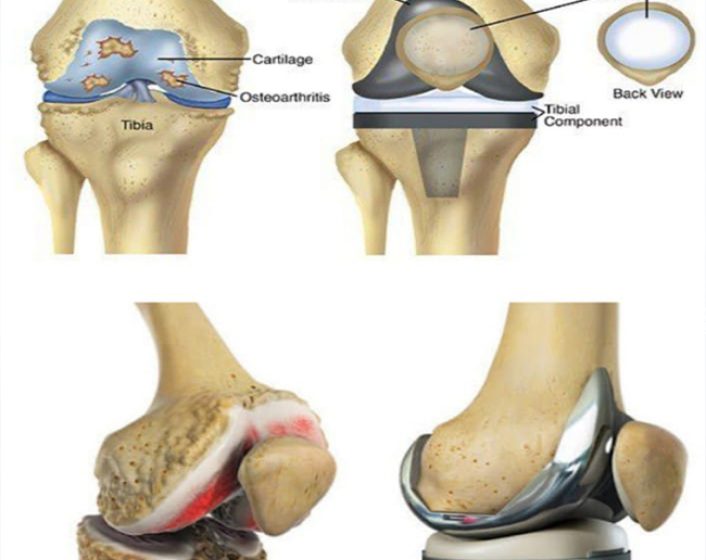

Knee replacement surgery involves removing damaged or worn knee components and replacing them with an artificial joint. It is typically recommended for patients suffering from severe arthritis or significant knee injuries that impair mobility and quality of life. The procedure aims to relieve pain, improve function, and restore mobility. Recovery involves physical therapy to strengthen the knee and regain movement. Most patients experience significant improvement in pain and function, allowing them to return to daily activities with enhanced comfort and mobility.

End stage arthritis of knee

Knee replacement treatment is designed for individuals with severe knee pain and dysfunction, often due to arthritis or injury. The procedure involves surgically removing damaged bone and cartilage from the knee joint and replacing it with an artificial implant. This surgery aims to alleviate pain, improve mobility, and enhance overall quality of life. Post-surgery, a comprehensive rehabilitation program is crucial for optimal recovery, including physical therapy to restore strength, flexibility, and function. With advancements in surgical techniques and prosthetic technology, most patients experience significant relief from pain and regain the ability to resume daily activities with greater ease and comfort.